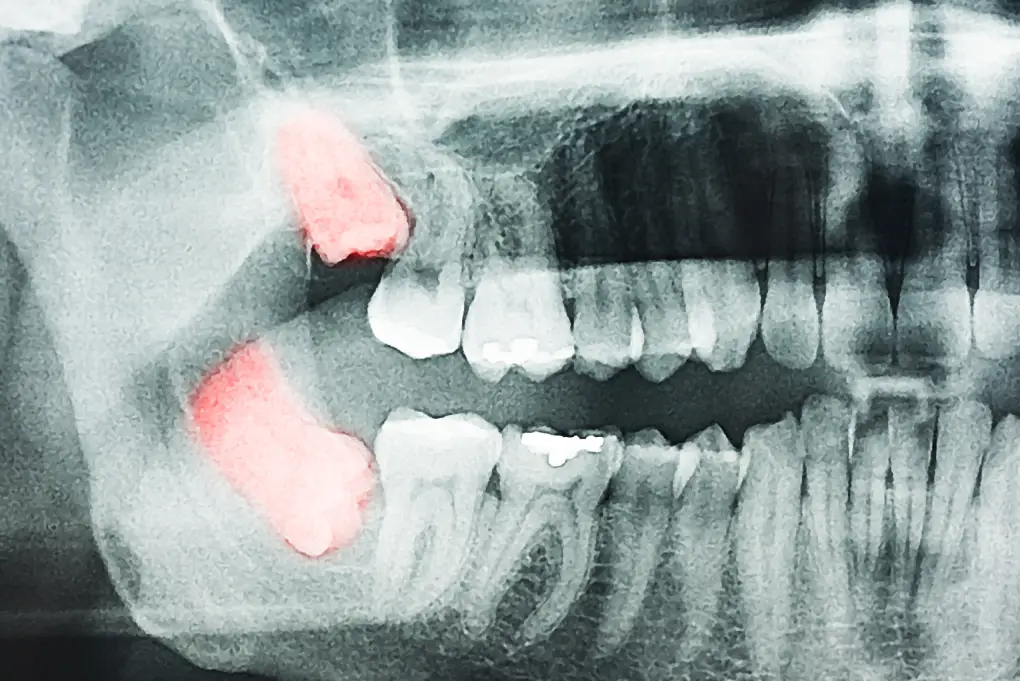

3) X-ray findings suggestive of impaction

An X-ray may show that a wisdom tooth is impacted or partially erupted. This does not automatically mean extraction is required, but removal is commonly recommended when the tooth is causing pain, recurrent inflammation/infection, decay, gum disease, or damage to neighbouring teeth.

Always discuss the findings and options with your dentist, who can explain whether monitoring or removal is the most appropriate approach for your situation.

Common impaction patterns include:

- Vertical impaction: tooth is upright (often less complex)

- Mesioangular impaction: tooth tilts forward

- Distoangular impaction: tooth tilts backward

- Horizontal impaction: tooth lies sideways against the adjacent tooth (often more complex)

More complex cases usually require more time and surgical steps, which can increase professional and facility fees. Your dentist can provide a clearer estimate after reviewing your X-ray.